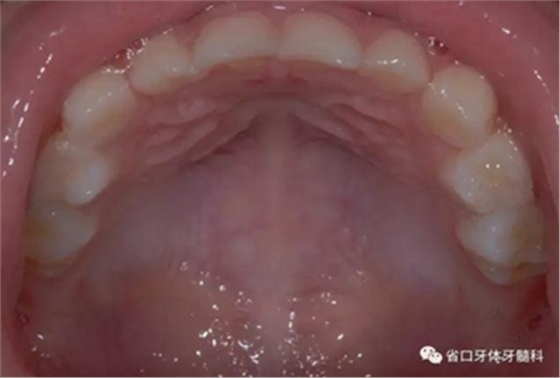

圖7 上頜牙相